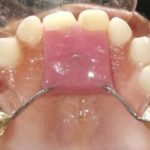

We at the Department of Pediatric & Preventive Dentistry focus on comprehensive oral health care needs of a child from infancy to adulthood and provide comprehensive, therapeutic as well as preventive care to all children including those with special care needs.

Treatment and Services